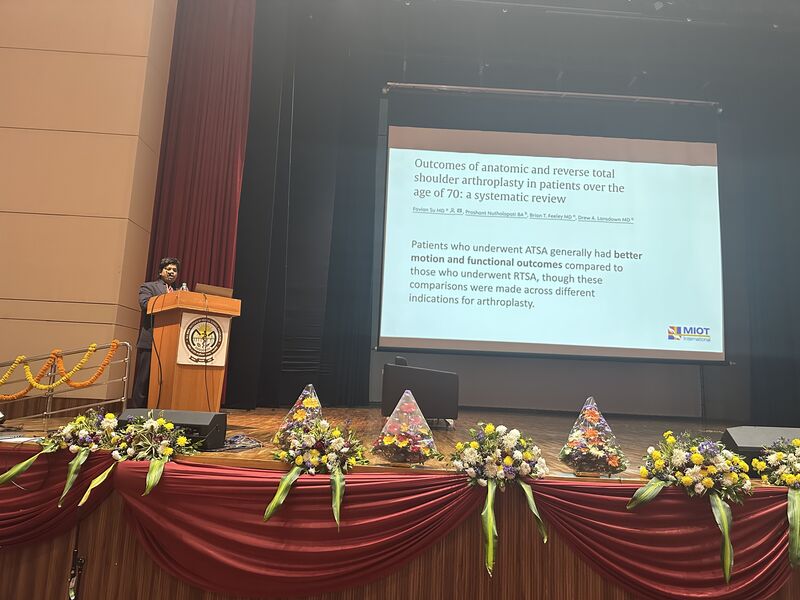

Had number of discussions on Reverse shoulder replacements , Just Unic , Transosseus cuff repairs and more

Two days filled with teaching and discussions